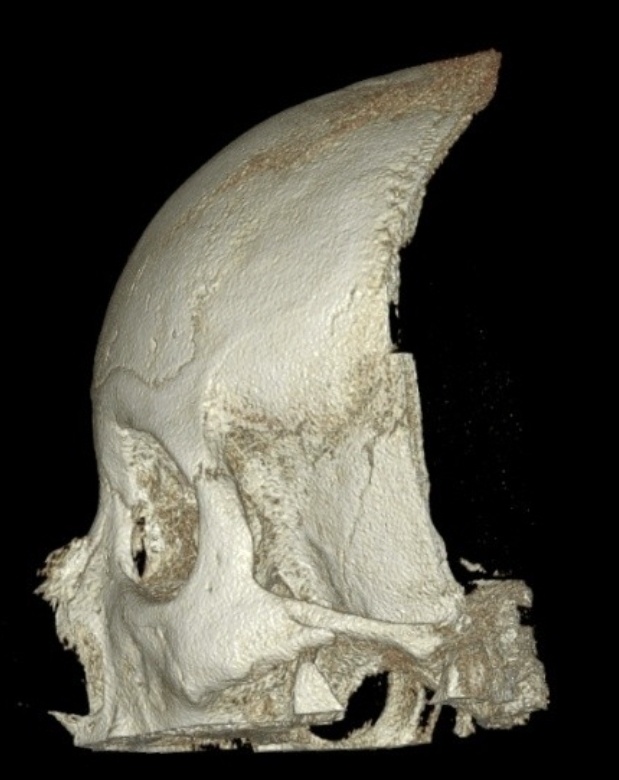

10년전 수술한 메틸본드 이마 성형 씨티사진 입니다.

0사진에서 보신것처럼 메틸본드를 제거하고 거상술을 받아도 눈썹위로?? 저런 볼륨이나

형태가 생기나요?? 아니면 메틸본드로 인한 것인지 궁금합니다.